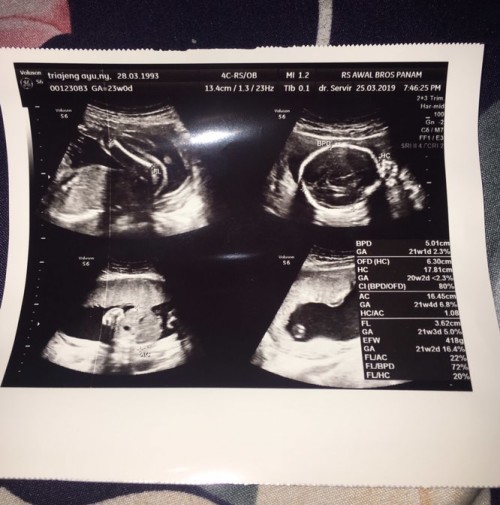

Jni usg 20-21mg bun

jenis klaminya udh kelihatan blum bun?